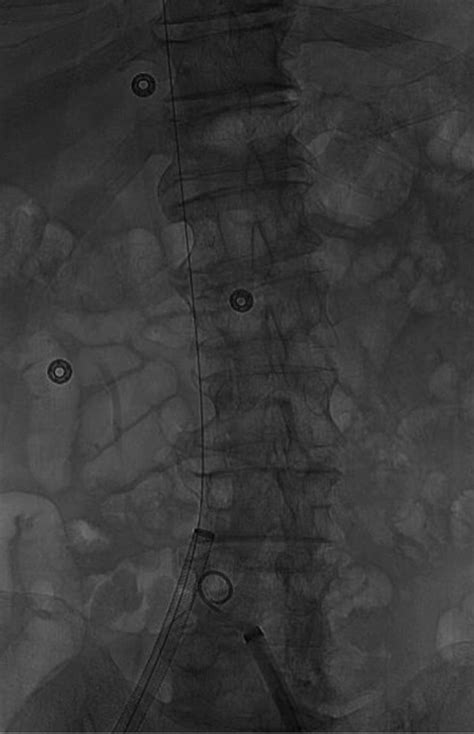

At its core, the IVC Greenfield Filter is a cone-shaped, metallic device inserted into the inferior vena cava, typically via the jugular or femoral vein. It is engineered to trap emboli—or blood clots—before they can enter the heart and subsequently the lungs, where they would cause a pulmonary embolism (PE). Unlike many other filters, the Greenfield design is renowned for its ability to maintain high flow rates while effectively catching clots, a feature that significantly reduces the risk of the filter itself causing a blockage.

• Conical shape: This geometry allows the filter to catch clots without completely occluding blood flow.

• Leg anchors: These secure the filter to the vein wall, preventing migration.

• Material composition: Initially stainless steel, modern iterations often use titanium or other biocompatible alloys to improve compatibility and visibility under medical imaging.

Techniques for placing and retrieving these devices have evolved significantly. With the use of ultrasound and fluoroscopic guidance, interventionalists can place the IVC Greenfield Filter with extreme precision through minimally invasive entry points. This has dramatically shortened recovery times and reduced the physical trauma associated with vascular procedures. Modern practice focuses heavily on the "retrieval phase," ensuring that patients are scheduled for follow-up appointments to discuss the removal of the device the moment their clinical condition allows.